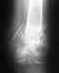

В мае 2005 года играя в баскетбол повредил левое колено.. Вначале оно вообще не сгибалось сильно распухло. Дня 2-3 передвигался по квартире опираясь на стул..Потом вроде прошло. К врачу естественно не обратился - думал растяжение связки. Но потом колено стало "выскакивать" вбок (в сторону правого колена) при неудачном шаге или резком... Ходил к первому врачу - сказал "разрыв внутреннего мениска", ко второму - сказал повреждение связки (кстати написал ОББ свзяки - я так и не понял что это за связка), третий сказал в военкоммате (как ни странно) что ничего нет, всё в порядке... кому верить куда обратиться? Колено впринципе не беспокоит постоянно, но всё же вылетает вот так неожиданно...это не дело. Помогите пожалуста, не могу так уже:)

Уважаемый Максим.Бесплатную.консультацию по Вашей проблеме можно получить в удобное для Вас время(кроме выходных) в Центре Косметологии и Пластической Хирургии.(Московская 19) Предварительная запись по телефону 228-28-28 к доктору Полякову Владимиру Юрьевичу .Для консультации желательно иметь рентгенологические данные.